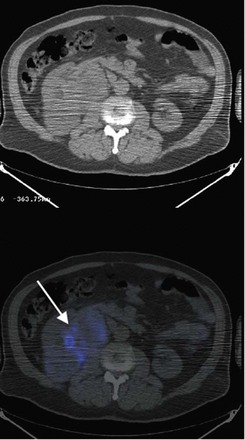

Tumor thrombus involving the IVC should be suspected in patients with lower extremity edema, varicocele, dilated superficial abdominal veins, proteinuria, pulmonary embolism, right atrial mass, or nonfunction of the involved kidney. MR venography is the authors’ preferred study for evaluating the presence and the distal extent of involvement of the IVC (Pritchett et al, 1987; Goldfarb et al, 1990) (Fig. 54–86). The use of invasive inferior vena cavography is limited to those patients with a nondiagnostic MR venogram or ultrasound evaluation, in those in whom MRI is contraindicated, and in patients who underwent preoperative angioinfarction with coils that would produce scatter leading to poor quality MR images (Fig. 54–87). Transesophageal echocardiography (Treiger et al, 1991; Glazer and Novick, 1997) and transabdominal Doppler ultrasonography (McGahan et al, 1993) are also useful. In patients with known IVC tumor thrombus the authors perform intraoperative transesophageal echocardiography to evaluate the distal extent of the tumor thrombus before making the incision.

First described by Barney and Churchill in 1939, the resection of pulmonary metastasis remains an effective treatment for select patients. Utilizing a thoracoabdominal approach for the radical nephrectomy and metastasectomy, the authors resect anterior lower lobe lesions using Doyle clamps and endovascular staplers. Favorable prognostic factors for isolated pulmonary metastasis include preoperative performance status, completeness of resection, number of lesions (less than six), limited lymph node involvement, and disease-free interval. Properly selected patients may have 5-year survival rates exceeding 50% (Hofmann et al, 2005). Metastasectomy in nonpulmonary sites such as the liver and brain are controversial and should be considered investigational. Preoperative imaging using biologic markers, such as monoclonal antibodies to carbonic anhydrase IX, may better help to identify occult metastatic disease and better stratify these patients with complex disease (Divgi et al, 2007) (Fig. 54–129).